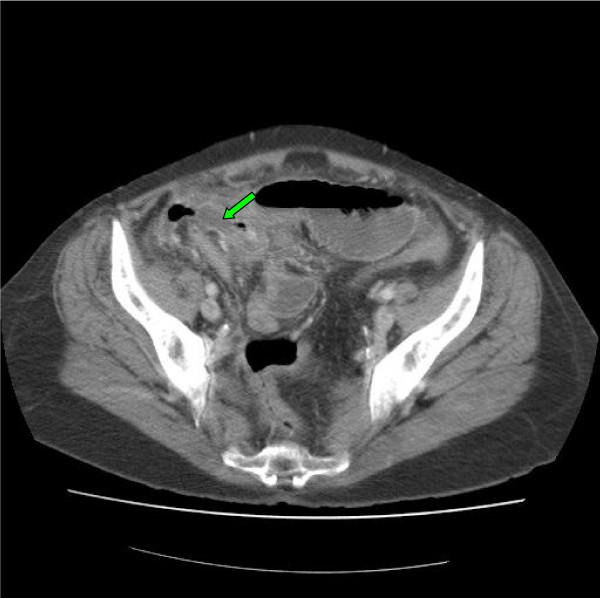

Acute appendicitis is a common surgical problem however the diagnosis is often overlooked when it presents as a small bowel obstruction. In this report we present two cases of elderly patients who presented with small bowel obstruction and raised inflammatory markers. Both patients were successfully treated with a laparotomy, adhesiolysis and appendicectomy and went on to make a good recovery.

急性阑尾炎是常见的外科问题,然而,当它表现为小肠梗阻时,诊断常常被忽视。在本报告中,我们介绍了两例老年患者,他们表现为小肠梗阻且炎症标志物升高。两名患者均通过剖腹手术、粘连松解术和阑尾切除术成功治疗,并顺利康复。